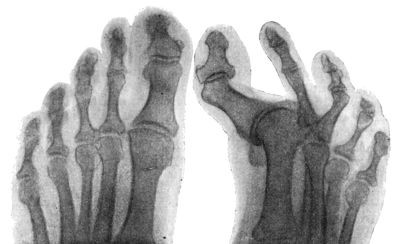

198 102.Radiogram of Dislocation of Toes

295 157.Radiogram of Hallux Valgus

296 158.Radiogram of Hallux Varus or Pigeon-Toe

298 159.Hallux Rigidus and Flexus in a Boy